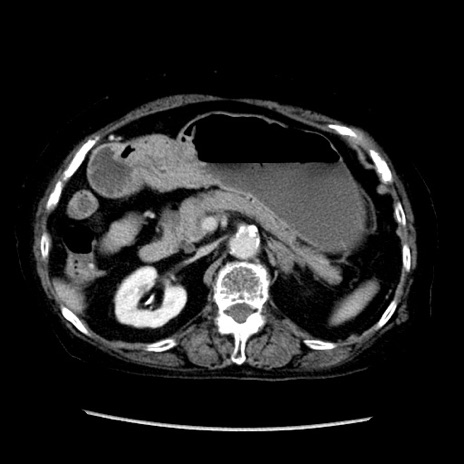

症例14(横断像)

【症例】 90歳代女性

【主訴】 腹痛・嘔吐

【現病歴】今朝から左側腹部痛を認めた。 経過観察していたが、嘔吐を認めたため来院。

【既往歴】 子宮癌術後

【身体所見】 意識清明、BP 127/54mmHg、P 98bpm Sp02 95%(RA)、BT 35.8°C、腹部平坦・軟腸ぜん動音聴取良好、右下腹部圧痛(+) 反跳痛なし

【データ】WBC 9800、CRP 0.46